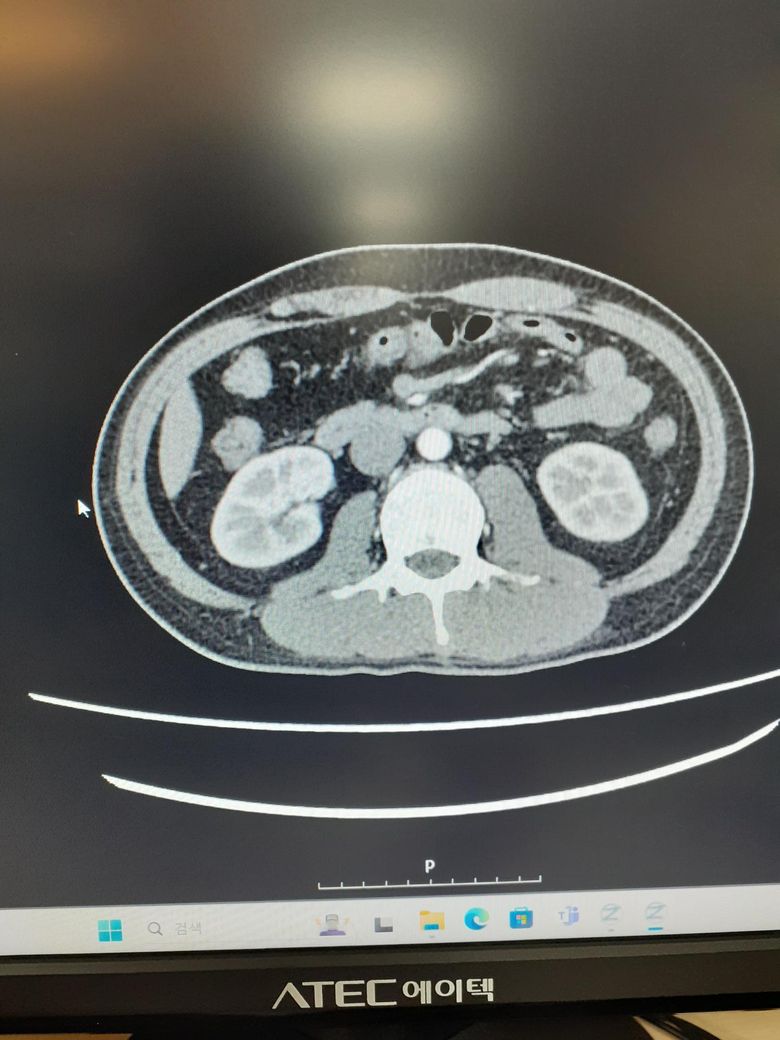

ct사진좀봐주세요사례합니다 조영제십니다

• 2번 째 사진

• 3번 째 사진